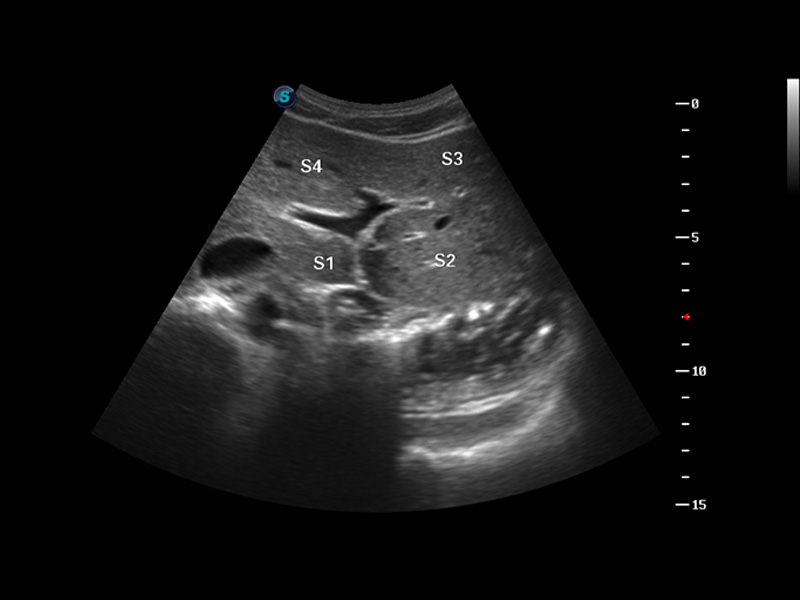

S8 EXP便携式彩色多普勒超声诊断仪是亚星官网研发的高端全身应用型便携彩超。高通道的VIS平台融合可视化(Visual)、智能化(Intelligent)和人性化(Smart)的特点,配以亚星官网自主研发生产的探头大家族,使您能够快速、准确的获得病人信息,提高工作效率的同时减轻疲劳。

μ-Scan微米成像

谐波成像

空间复合成像